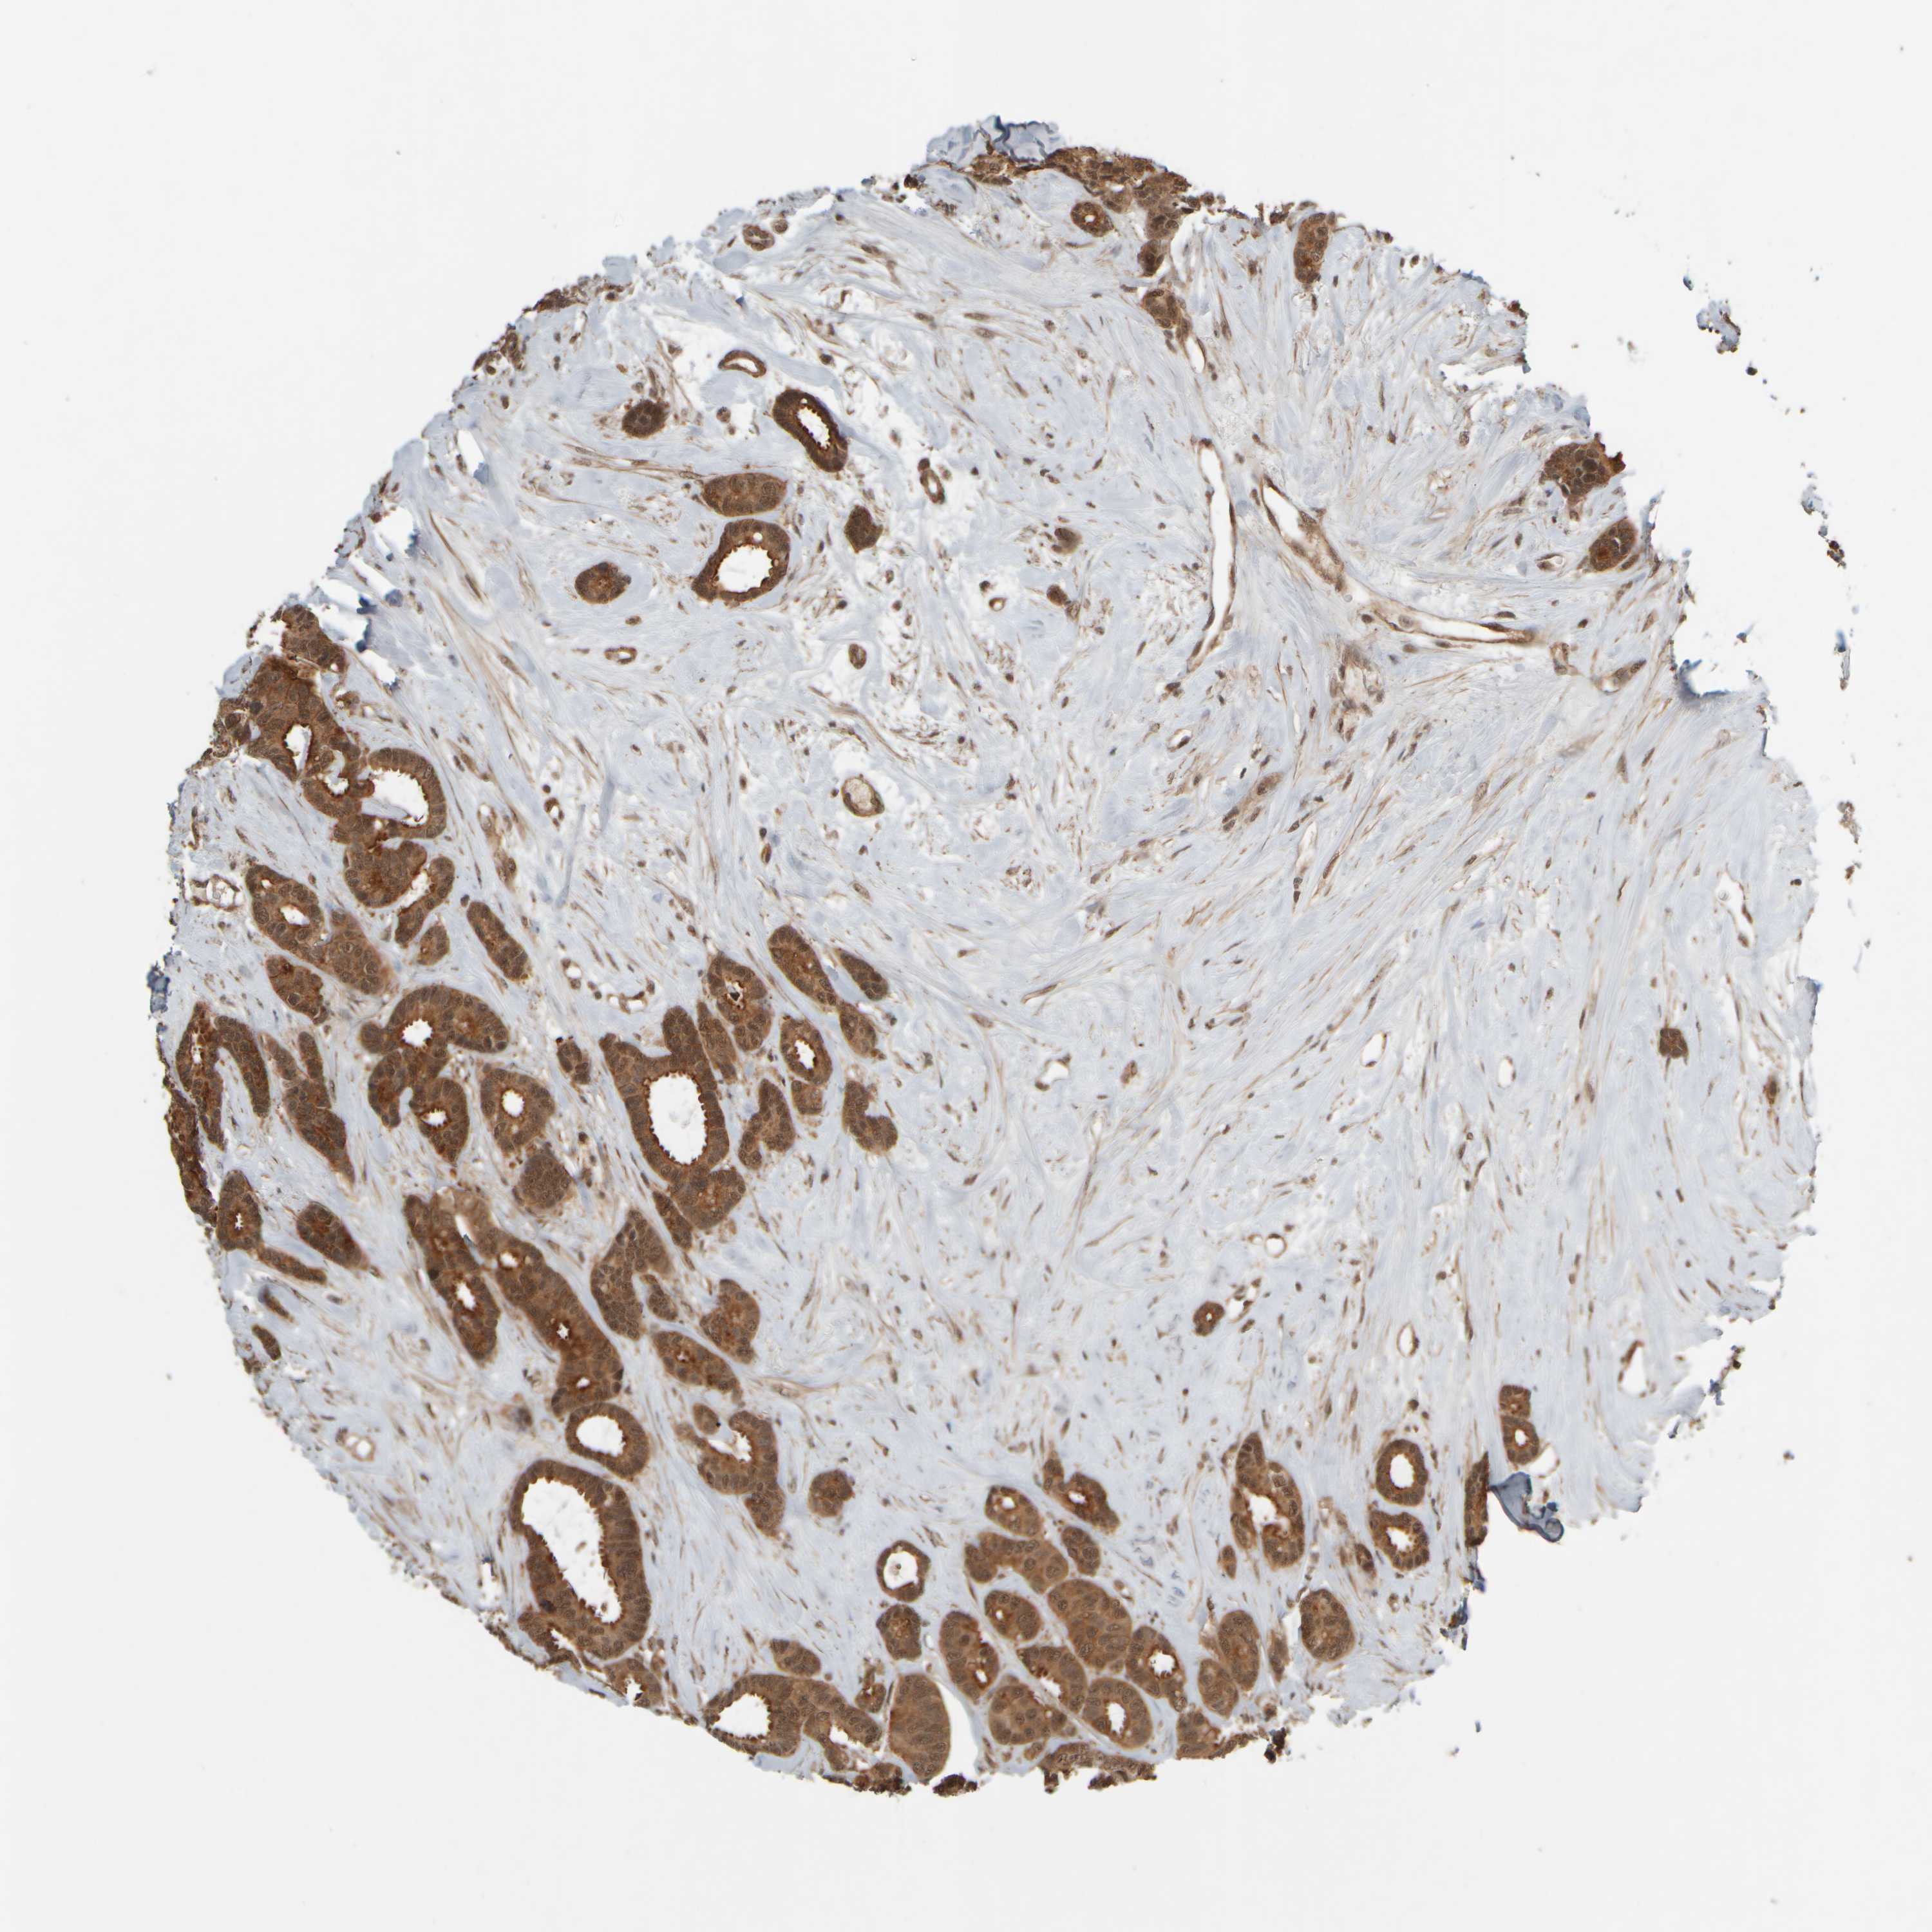

CANCER BREAST CANCER Show tissue menu

BRCA TCGA BRCA VALIDATION PROTEIN EXPRESSION